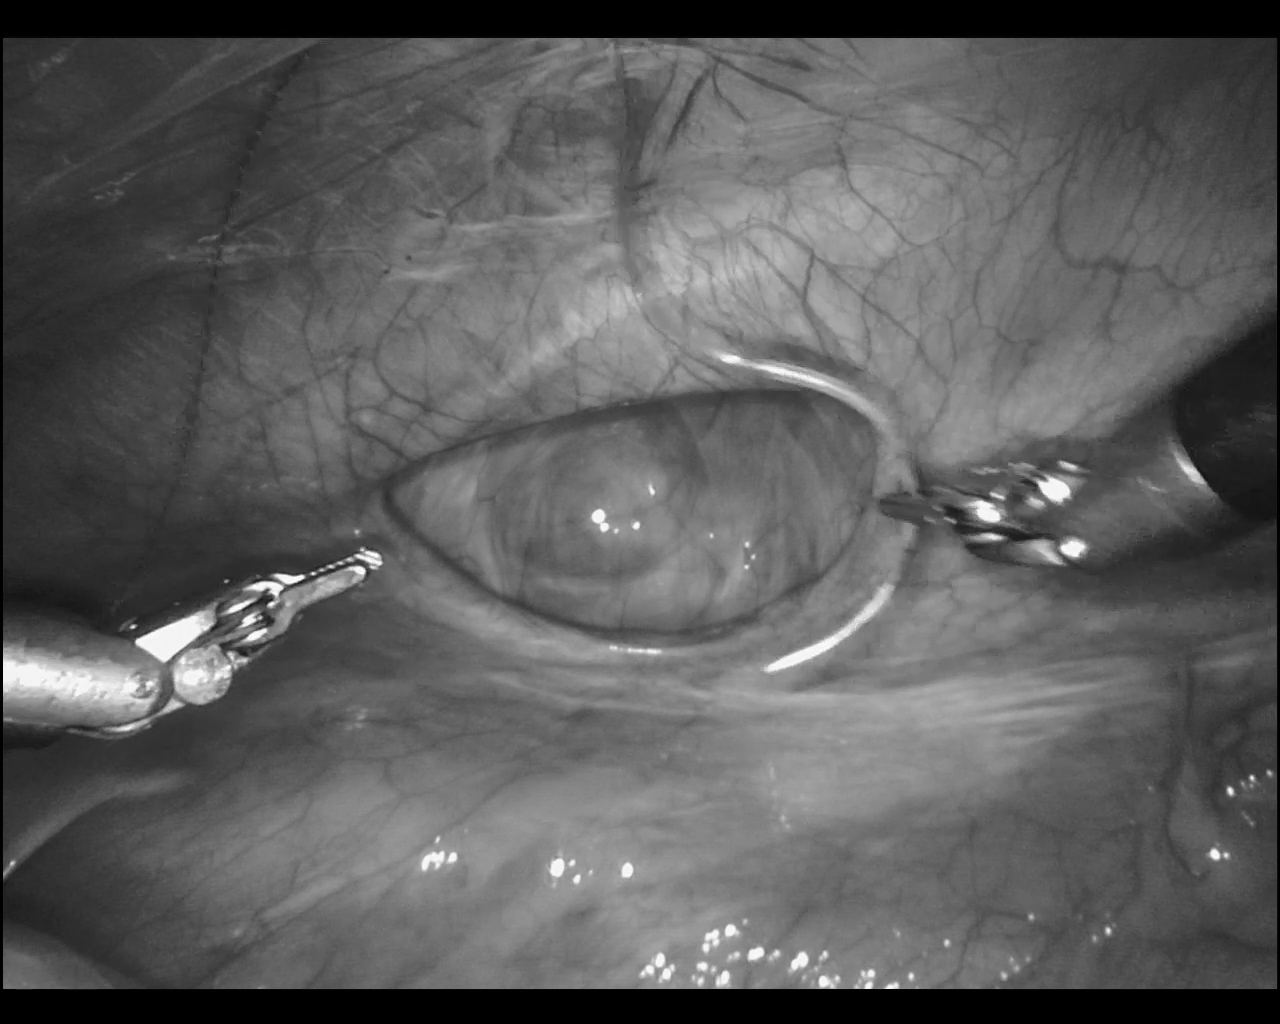

Specular Reflections Detection and Removal Based on Deep Neural Network for Endoscope Images

Tianyu Liu, Junyu Chang, Chongyu Wang and Liangjing Yang*

IEEE EMBC, 2021

Aimed to detect and restore specular reflections caused by metal instruments or smooth tissue membrane during surgical operations based on Deep Neural Network.

Proposed a novel model based on deep learning framework, known as Surgical Fix Deep Neural Network (SFDNN).

Designed and modified a deep neural network model to detect the reflection points in a surgical video.

Used the time series scheme to repair the reflection part, restoring the real surgical scene.